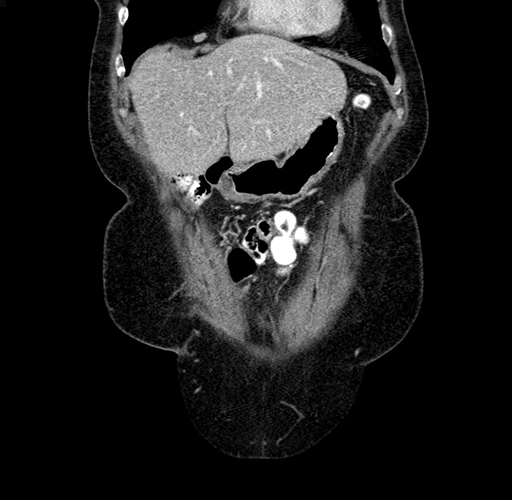

Pre-Chemo: Coronal Venous

Coronal Venous